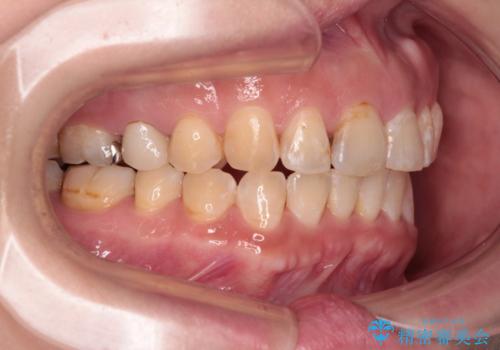

- 飛び出た上の前歯を気にして来院された患者様です。

奥歯の咬み合わせは、上顎歯列が理想的な一よりも数mm前方にある状態でした。

舌の突出癖が原因で上下の歯に大きなスペースが生じていたため、舌のトレーニングをしっかり行っていただくことで、上顎歯列をスムーズに移動させることができました。